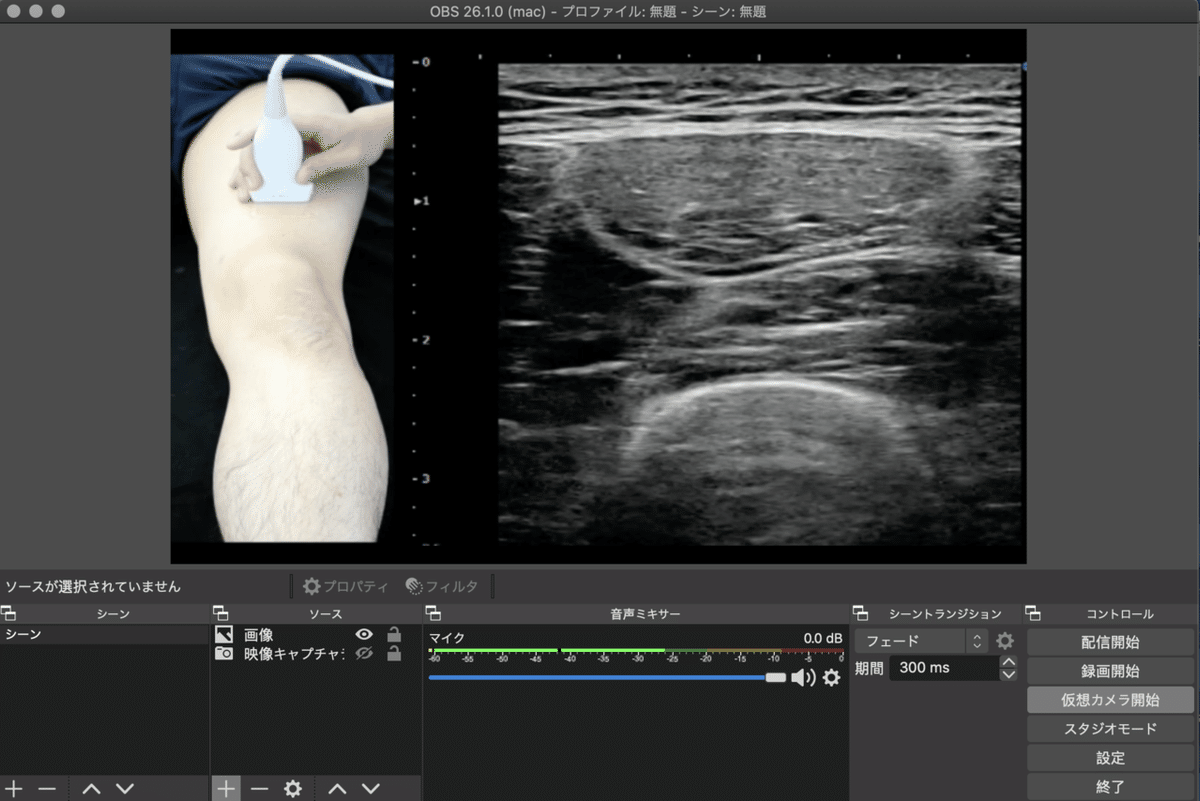

下図がOBS-stadio26.1(OBSバージョン26.1)です。

画面右下の『仮想カメラ開始』が表示されています。

そこをクリックするだけでOBS側の設定は完了です。